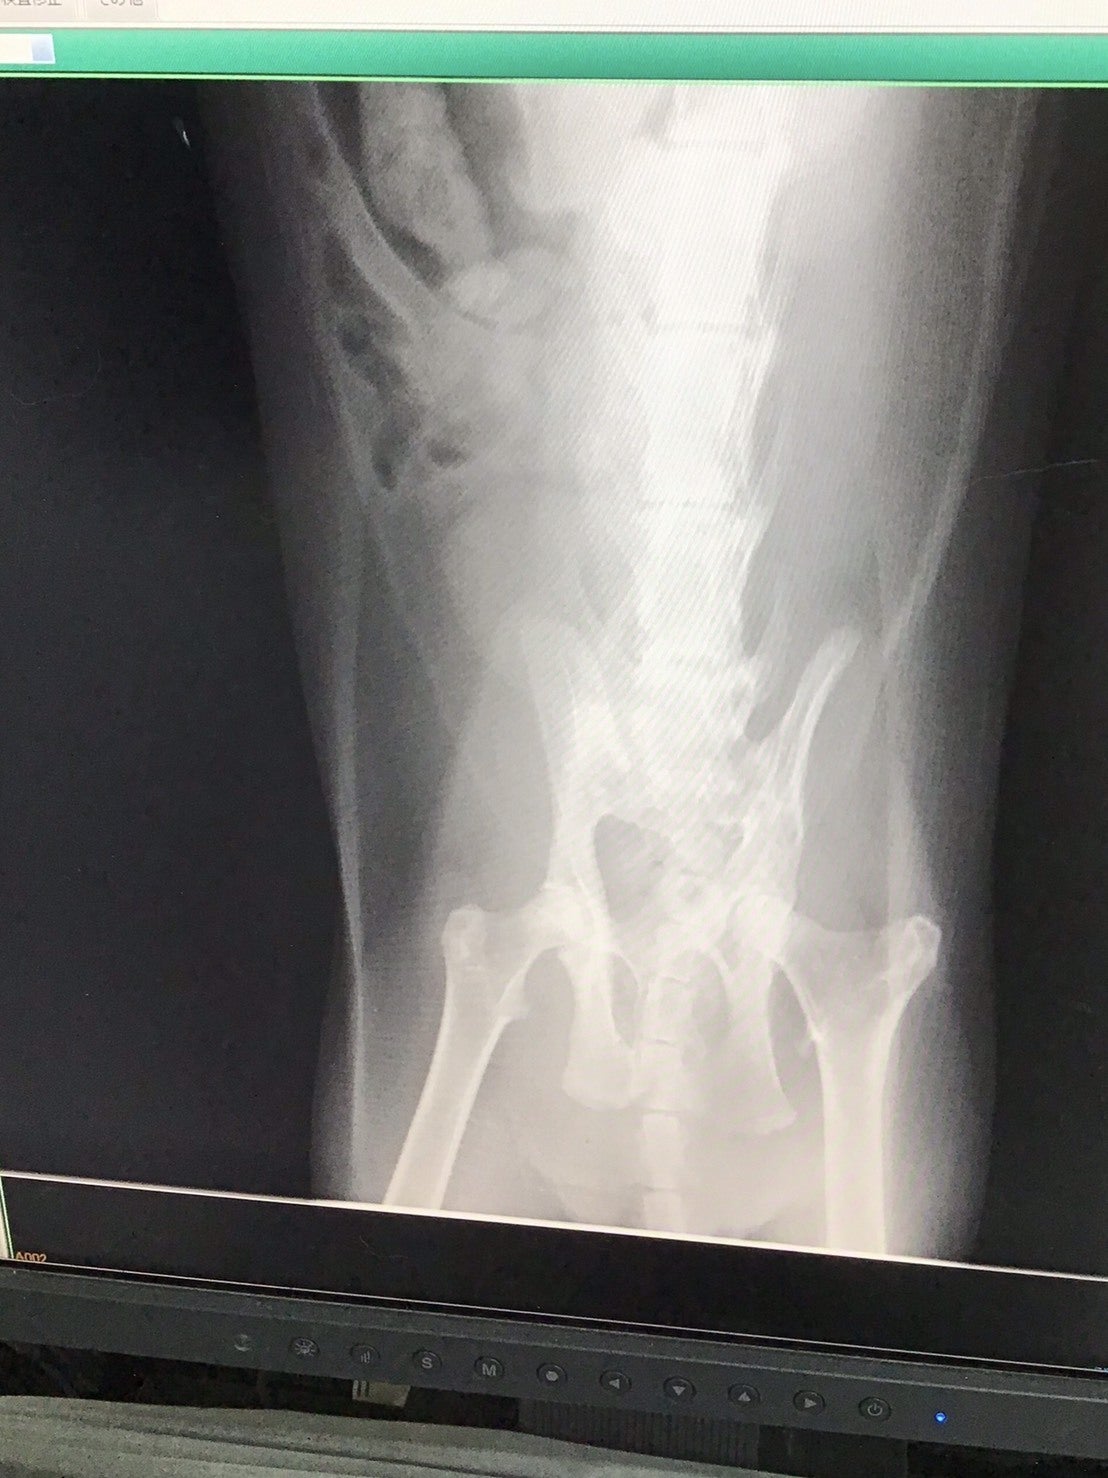

具合が悪そうで、最初原因不明でしたが、脚の動きが悪く便の出も悪かったので、レントゲンを撮りました。診断は骨盤骨折。外傷はなかったので、外からは分からなかったのですが、大変な怪我をしていたのです。事故でしょうか⁈ それとも 踏みつけられたりしたのでしょうか⁈

めるちゃんは折れた骨盤が直腸を圧迫して、便の通り道が狭くなっていました。うまく排便できないので、繰り返し腸に便が詰まってホースのように太くなる巨大結腸症に陥ります。いきんでもいきんでも便が出せません。フードを制限し、投薬、サプリやマッサージなど、便を出すため試行錯誤をしてきました。全く便が出せなくなると、嘔吐し食べれなくなるので、何日もかけて自力でようやく少量づつ排便できる様、長期入院と退院を繰り返してきました

現在3歳。たくさん食べて、まだまだ遊びまわりたい盛りです。この状態を改善するには、便が楽に通れるよう、狭くなった骨盤を広げる手術が必要ですが、設備と機材等が整っている病院でないと手術はできません。手術や治療など高額になります。